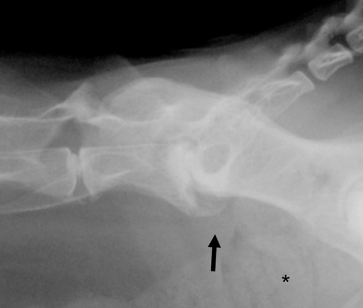

통상적으로 이야기 하는 ventral spur 즉, spondylosis deformans와 동일한 양상의 병변이라는것이다.

이 논문에서 제시하는 사진들은 대부분 증상이 없다면 spondylosis deformas 의 양상이라는것이다.

다시 말해 discospondylitis가 진행하여 치유된 후에는 spondylosis deformas 양상으로 보인다는 말이 된다.